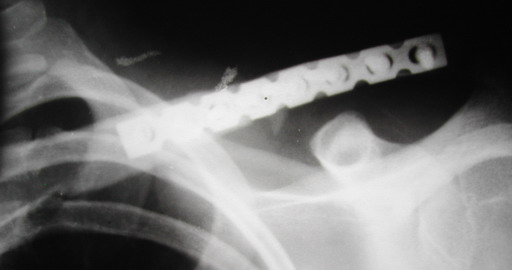

Во время стажировки в Австрии не мог не поинтересоавться, как австрийские хирурги лечат переломы ключицы. Оказалось, при переломах без смещения или с небольшим смещением накладывают восьмиобразную повязку, в остальных случаях выполняют остеосинтез пластинами.